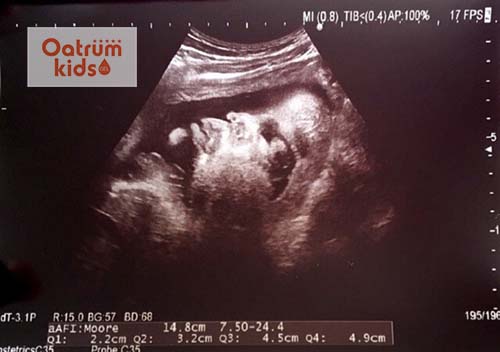

+ Thực hiện siêu âm 2D: nhằm mục đích kiểm tra ngôi thai, xác định vị trí thai, xác định hình thái bên trong và bên ngoài của thai, nhịp tim thai nhi và các vấn đề liên quan khác.